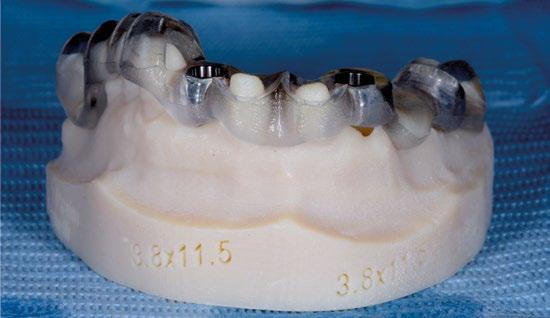

Se planea la rehabilitación definitiva con soporte implantario con la ayuda de cirugía guiada e implantes Prama Short Neck. En las posiciones 12 y 22 se colocan implantes de 3,80 mm de diámetro y 11,5 mm de altura, mientras que en la posición 15 se planea la colocación de un implante de 10 mm de altura inclinado mesialmente para evitar el seno maxilar.

Planificación del posicionamiento de los implantes en cirugía protésicamente guiada.

Dima quirúrgica en modelo impreso con impresora 3D.